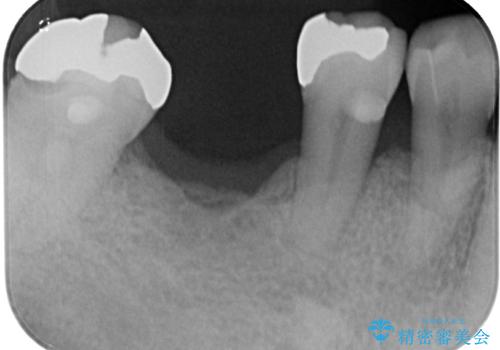

- 奥歯を抜歯してから放置しているとのことで来院された患者様です。

歯が割れて抜歯になってしまったとのことで、咬合力に抵抗できるよう、インプラントによる補綴治療を行うこととしました。

むし歯の放置期間と抜歯してからの放置期間が長く、咬み合わせる上顎の歯がやや伸び出している状態でした。

上顎の部分矯正や対合歯の補綴治療も提案しましたが、今回は欠損部のみの治療を行いました。